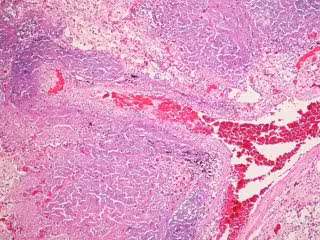

FLICKER/ PULMONARY PATHOLOGY